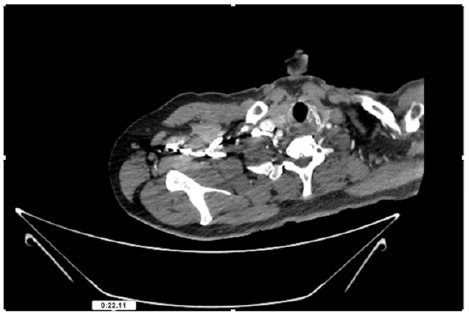

55-years-old chronic smoker had acute, severe pain in the right upper limb for one week; it was cold upto mid arm with skin discoloration. He also noticed numbness and weakness of movement of elbow joint. He underwent below elbow amputation in February 2023 for acute ischemia of left upper limb. He was a current chronic smoker; 15 pack year. General condition was weak; temperature was normal; blood pressure was 100/60mmHg; heart rate was 92/minutes with sinus rhythm; SpO2 was 97% on air; heart was normal. In lower extremities, all peripheral pulses were intact. Local Examination of right upper limb revealed as follows: tenderness; coldness; discoloration; decreased motor function and sensory modalities. Axillary, brachial and radial pulses were not palpable. Hand-held Doppler failed to detect any signal in arterial system; therefore, we arranged for emergency embolectomy. complete occlusion of right upper limb arterial system Full blood count showed high hemoglobin (14.6gm%); normal total WBC and platelet count. Coagulation profile was normal. Parenteral unfractionated heparin, antibiotics, tramadol, proton-pump inhibitors, anti-platelets and HMG CoA reductase inhibitors were given. Doppler ultrasound demonstrated complete occlusion of right upper limb arterial system. CT Angiogram illustrated occlusion of subclavian artery downwards on both sides. Figures 1-14 shows complete occlusion of right subclavian artery without collaterals. On Day ‘2’ of admission, the patient passed black tarry stool for 3 times. However, the vital signs were stable; blood pressure was 100/60mmHg; heart rate was 92/min; SpO2 was 97% on air; the abdomen was soft and not tender. Above elbow amputation was done on Day ‘2’ of admission. Intra-operative findings were as follows: (1) no active bleeding at brachial artery; (2) thrombosis along brachial artery; (3) muscle color and consistency were not healthy.

Figure 4: CT Angiogram at neck showing normal brachio-cephalic trunk, common carotid artery, and narrow right subclavian artery.

Figure 5: CT Angiogram at neck showing normal brachio-cephalic trunk, common carotid artery, and narrow right subclavian artery.

Figure 6: CT Angiogram at neck showing brachio-cephalic trunk, common carotid artery and narrow right subclavian artery.

Figure 7: CT Angiogram at neck showing brachio-cephalic trunk, common carotid artery and narrow right subclavian artery.

Figure 10: CT Angiogram at upper arm showing totally occluded right axillary artery; normal internal carotid artery and external carotid artery.